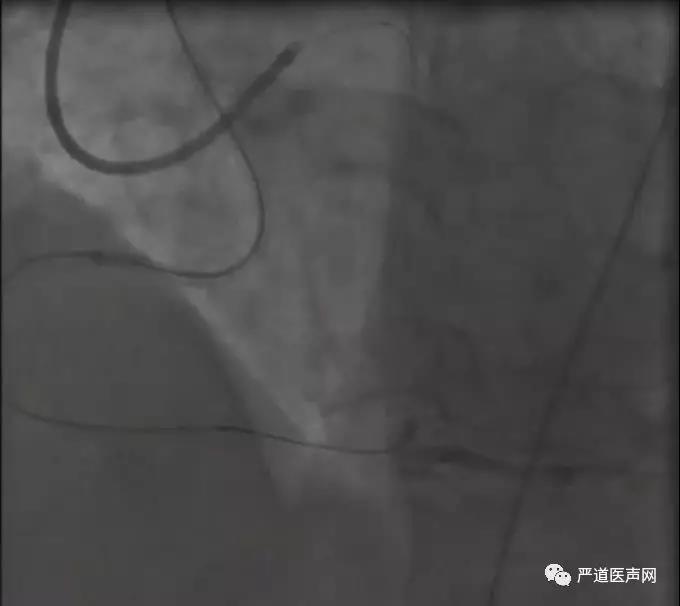

柳景华教授团队手术中

手术过程

桡动脉入路逆向使用Runthrough导丝配合1.5米Corsair微导管尝试通过侧支,在侧支中的迂曲部位遇到较大阻力。

更换Sion导丝成功通过侧支,此时1.5米微导管已经无法前行,使用延长钢丝更换1.7米APT微导管。

Tip injection观察闭塞段远端结构发现远端呈锥形,选择PILOT150导丝(190cm),配合170cmAPT微导管,此时留给术者操控导丝的距离仅10cm左右,导丝每前进1cm,微导管就需要跟进1cm。由于闭塞段内钙化较重,升级为GAIA3导丝继续尝试推进遭遇较大阻力,立即开始正向准备。

正向采用PILOT 150导丝结合135cm Corsair微导管进入闭塞段,最终可能进入了一个很小的分支也有可能在假腔(此时周围有许多前次CTO介入时造成的假腔)。

正向升级为Conquest-Pro导丝尝试与逆向导丝Kissing,多体位投照证实Kissing成功。